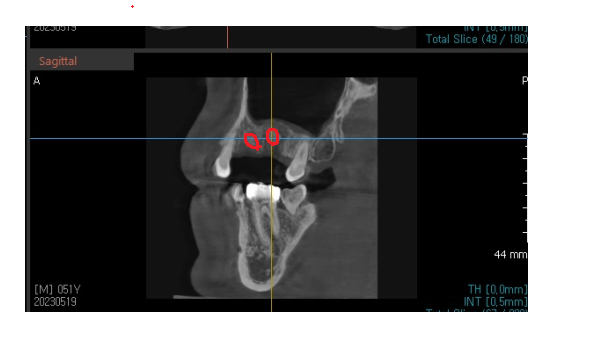

230529

ct에서도 뼈이식한 흔적들이 잘 보입니다.

그렇지만 아직은 부족하여

2달을 더 기다립니다.